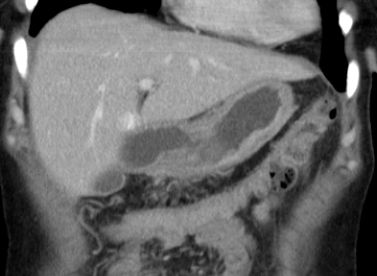

Colon 79-jährige Frau mit einem Tumor im Zoekum. Bei der Operation fand sich im Bereich der Ileozökalklappe ein unregelmäßig gestalteter, teils ulzerierter und teils polypös erhabener, 42 mm großer, derber Gewebsbezirk. Histologie: In soliden Komplexen und Strängen angeordnete, relativ große Tumorzellen mit deutlicher Zell- und Kernpolymorphie. Vergrößerte Zellkerne mit aufgelockerter Chromatinstruktur und ab und an prominenten Nukleolen. Schmaler oder kaum erkennbarer Zytoplasmasaum. Vermehrt typische und atypische Mitosen. Tumoreinbruch in Blut- und Lymphgefäße. Das CT zeigt multiple Lebermetastasen.